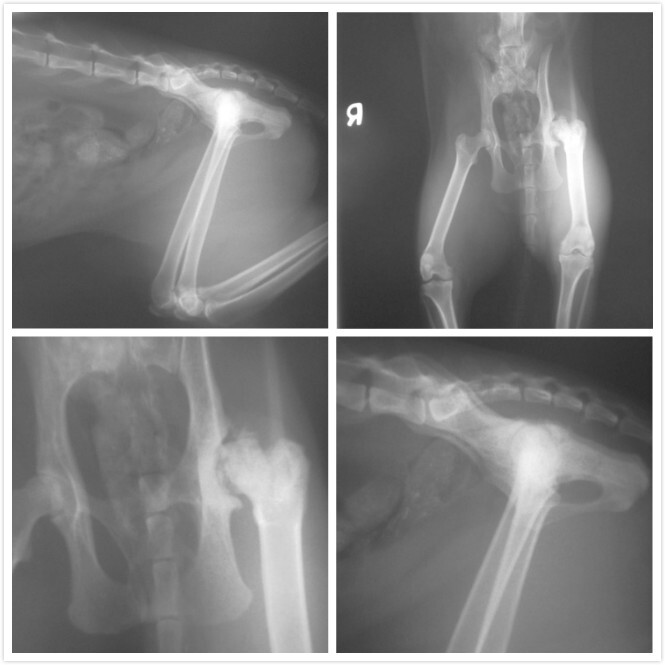

小黃左腳有不正常骨贅增生造成骨關節炎,因疼痛以致造成左腳跛行,股骨頭摘除,為解決疼痛及改善跛行的方式之一,因食慾狀況並不穩定所以今日先上點滴並驗血做術前評估,初步驗血結果肝腎指數均正常且無貓愛滋及白血病

因為小黃可能是之前受傷~當下我又不以為意只投消炎藥沒就醫~不知道那時後股骨頭受傷造成後來不正常骨贅增生造成退化性骨關節炎~所以才會因疼痛以致造成左腳跛行~大腿也有點肌肉萎縮~~

醫生說如果沒開刀~往後就是後腿會越來越萎縮~變成三隻腳走路~

因為小黃送醫時都不吃~所以醫生先評估~狀況穩定已於昨天12/19開刀把股骨頭切除~~但開完刀後拍片子發現到有碎骨~所以今天又必須在一次受術把碎骨清乾淨~~